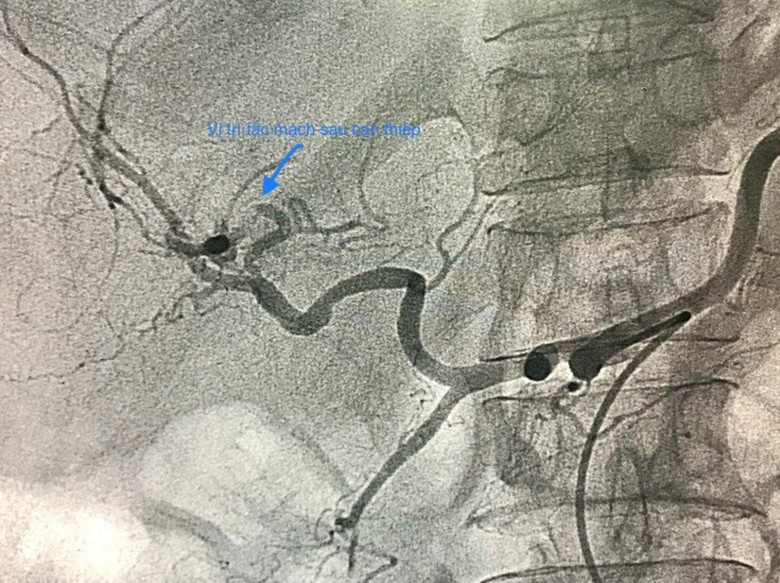

Và sau khi được can thiệp

GS Phạm Như Hiệp, Giám đốc Bệnh viện Trung ương Huế cho biết, bệnh nhân xuất hiện tình trạng xuất huyết do vỡ túi giả phình động mạch gan do áp xe gan cần hồi sức tích cực và giải quyết phình mạch gan bị vỡ. Thuyên tắc nội mạch là lựa chọn điều trị đầu tay với tỷ lệ thành công là 95%.

Trường hợp này đã được xử trí thành công bằng thuyên tắc nội mạch qua da. Không được bỏ qua mối liên quan giữa giả phình động mạch gan và áp xe gan, lưu ý đến biến chứng vỡ phình có khả năng gây tử vong và có thể ngăn ngừa bằng cách can thiệp kịp nút mạch qua da kịp thời.